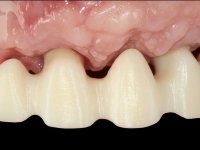

O paciente foi observado conjuntamente e a dúvida que surgiu de imediato foi se seria possível com a regeneração óssea a efectuar poder ser reabilitada naturalmente a zona das papilas interdentárias. Nesse sentido foi feito um enceramento de diagnóstico que contemplaria as duas hipóteses, utilizando ou não a cerâmica gengival. A confecção desse enceramento foi fundamental para expor ao paciente a dificuldade da reabilitação. O wax-up deu origem a um mock-up que foi aprovado pelo paciente e que simultaneamente serviu de guia imagiológica. O caso foi planificado cirurgicamente e realizada uma guia cirúrgica com que foram colocados os implantes. Após 10 semanas foi feita a 1ª impressão para confecção da ponte provisória. Foram criados os primeiros perfis de emergência na gengiva artificial e foi digitalizado o modelo. Por processo de CAD-CAM foi confeccionada uma ponte provisória aparafusada baseada no enceramento de diagnóstico. A ponte trabalhou durante 8 semanas os tecidos moles que foram fielmente copiados numa impressão com técnica de moldeira aberta. Os transferes foram individualizados com resina composta para copiarem fielmente os perfis de emergência criados pela ponte provisória. Confeccionado o modelo de trabalho definitivo, foi realizada uma infra-estrutura em zircónio seguindo a orientação do enceramento de diagnóstico. O assentamento da infra-estrutura foi testado em boca e simultaneamente foi novamente impressionados os tecidos moles com um silicone fluido. Nessa consulta foi feito o levantamento da cor. Os dentes 13 e 23 apresentavam uma saturação anormalmente forte que resolvemos não valorizar, optando por privilegiar a relação com o sector antero-inferior. Foi realizada uma nova gengiva artificial com a impressão que acompanhou a impressão de arrasto com a infra-estrutura. Após a colocação da cerâmica na infra-estrutura foram coladas as meso-estruturas. O trabalho final foi aparafusado lentamente permitindo a adaptação dos tecidos moles.